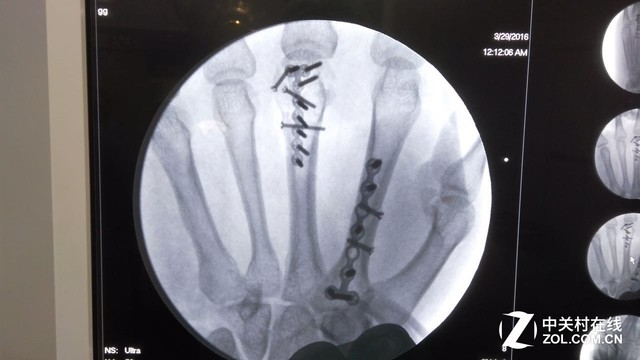

其实,第一期栏目视频做的很仓促,但王小白确实尽力了,视频中的我显得很没精神,节目录制的前不久刚刚接手了左手2、3掌骨的内固定手术,由于节目录制原因提前拆掉了石膏以及纱布,有心的网友们或许会在视频中看到左手背一条长达5公分的手术伤疤……

视频录制前不久王小白刚刚接受了左手2、3掌骨的内固定手术

19根钢钉、2根钢板被植入了手掌中